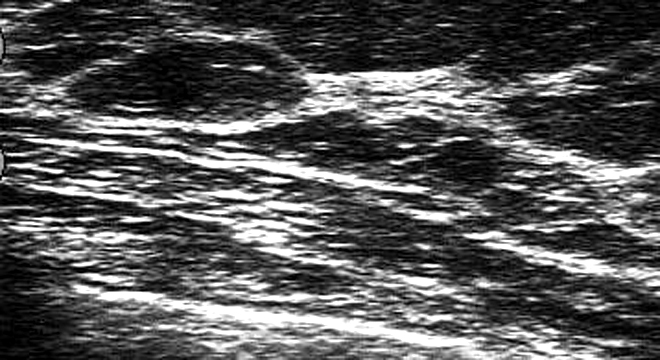

Zur Diagnose von Brustzysten werden verschiedene Untersuchungen und Abklärungen durchgeführt. Dazu gehören unter anderem:

• Krankengeschichte unter Einbezug der Symptome

• Abtasten der Brüste

• Ultraschall

• Mammographie, zum Ausschluss anderer Erkrankungen, insbesondere andere gutartige Veränderungen oder bösartige Tumore

• Punktion der Brustzyste und mikroskopische Untersuchung der Flüssigkeit

• Pneumozystographie: Injektion von Kontrastmittel sowie Luft (deshalb pneumo) in die Zyste; danach Röntgenbild zur Begutachtung der Zystenwand. An der Zystenwand können sich sogenannte Papillome bilden; das sind gutartige Gewächse.